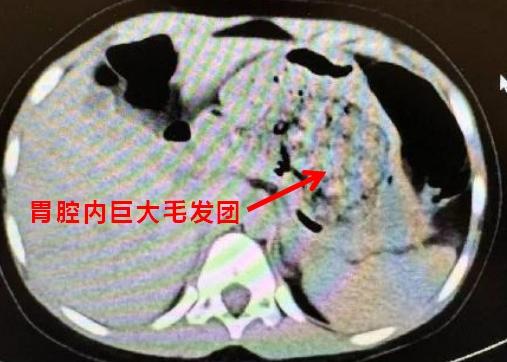

医生听到这里,震惊的同时豁然开朗,原来在CT阅片的时候,发现了孩子胃里面有一团密度较高的团块,结合母亲提供的病史,医生断定孩子长期吃头发导致了胃内毛发成团,这也是这次腹痛的原因。

得出了初步诊断后,医生立即安排孩子住院,联系消化内科医生做胃镜检查,如果能够明确诊断,可以先尝试胃镜下取出,达到“无创”的效果。结果,当胃镜进入的瞬间,所有人都惊呆了,孩子胃内的毛发包裹食物残渣形成了一个巨大的团块,充满整个胃腔。